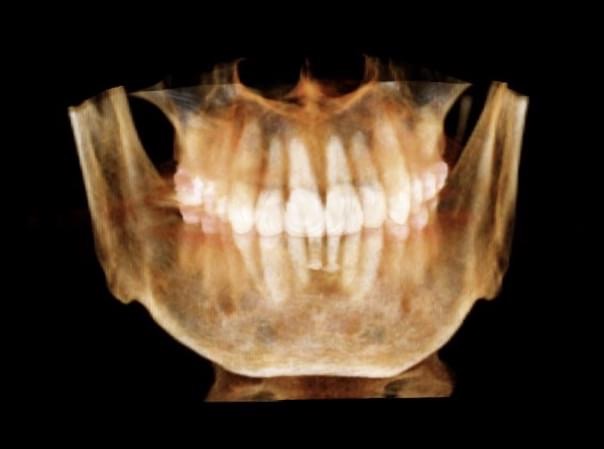

A dental implant is an option to replace a missing tooth. In this procedure, a small titanium screw is surgically implanted into the bone and allowed to set. The bone grows around it forming a tight connection, which additionally slows or stops the bone loss that occurs when the root of a natural tooth is missing. Once the implant is firmly set in the mouth, the dentist then works to attach the replacement tooth onto the top of the implant.

Dental implants are considered to be the most important advance in dentistry in the past 100 years. They allow us to predictably replace missing teeth in a very esthetically pleasing manner without compromising the integrity of the adjacent teeth and without the aid of removable appliances.

Implants can also be used as support as part of an implant bridge.